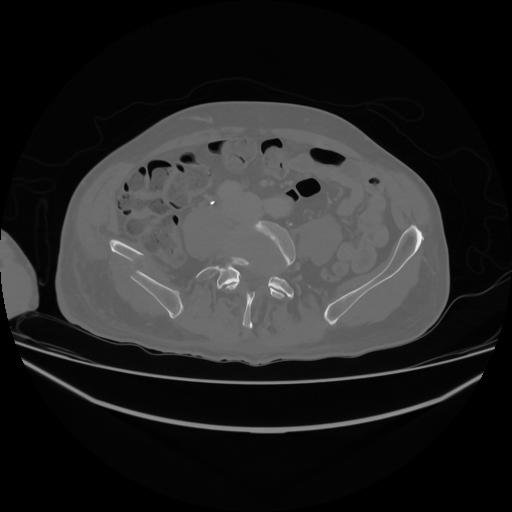

5 CUERPO,CE,Vol,1.0,CUERPO,,